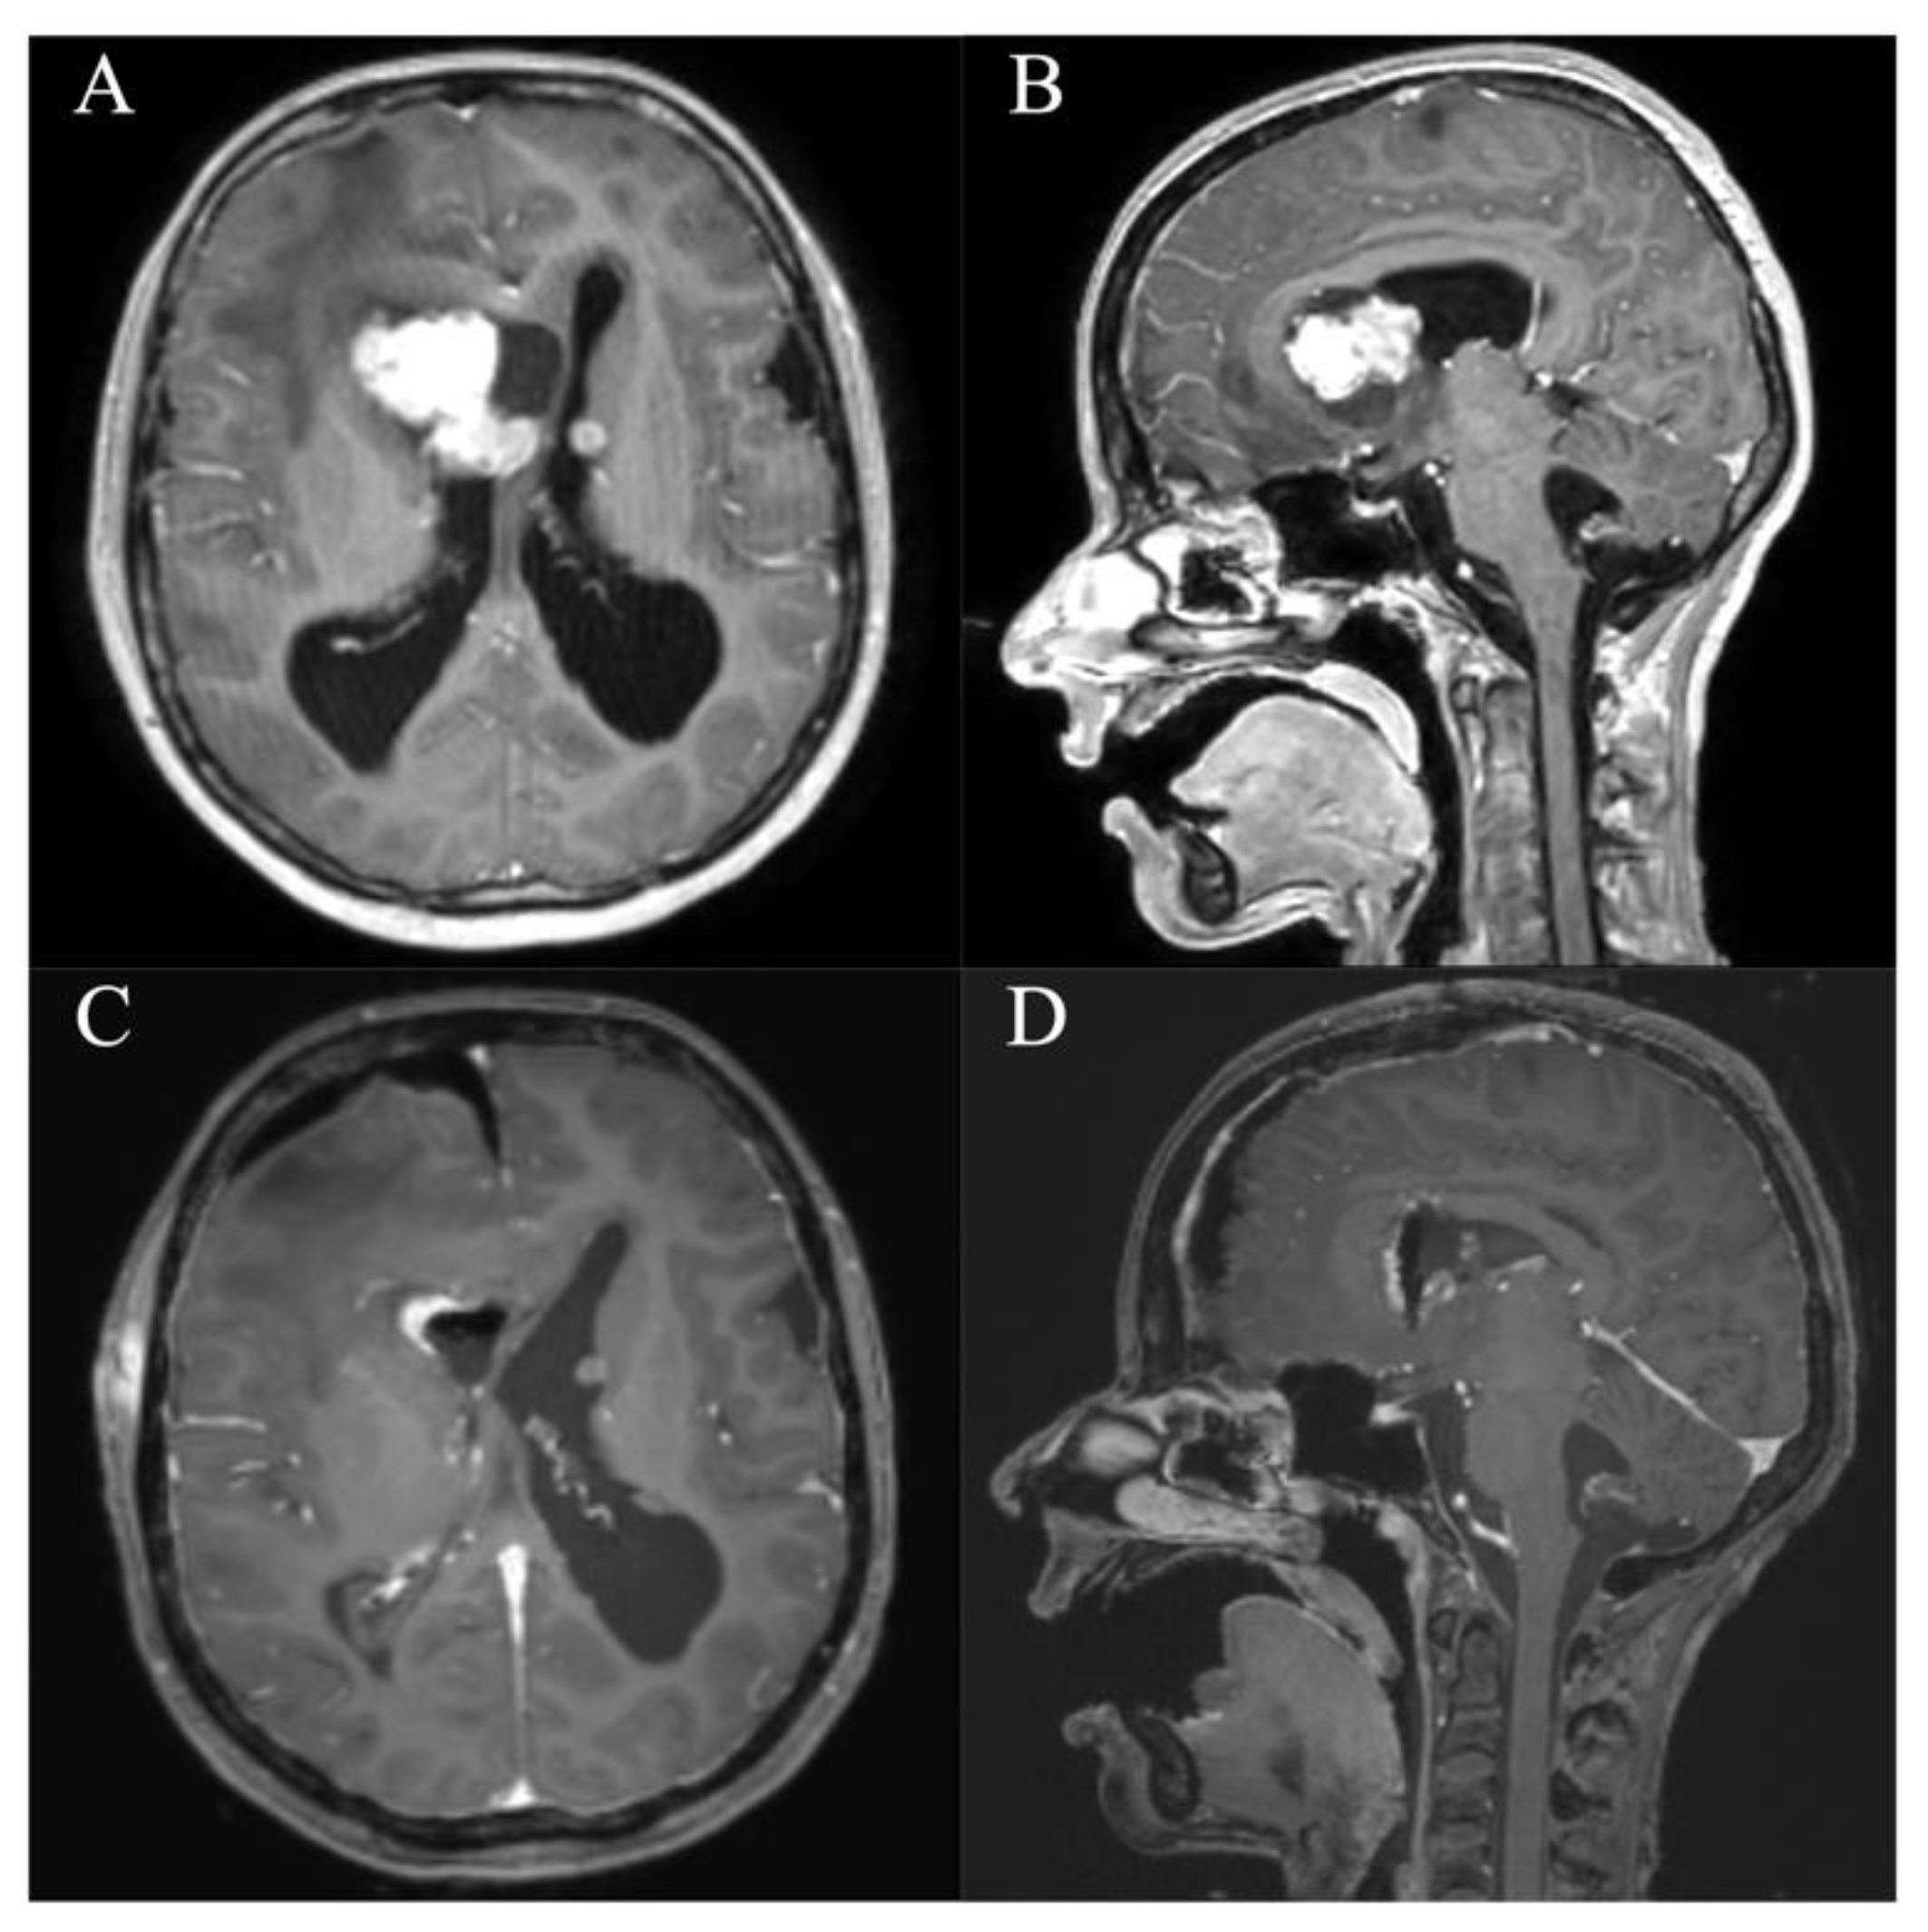

In all patients, a GTR/NTR could be achieved (Table 3). The pre- and postoperative scans of cases no. 3, 6, and 7, which were all treated through an EA approach and case no. 8, which was treated through a PE approach, are shown in Figure 3, Figure 4, Figure 5 and Figure 6. In one patient (case no. 5), due to her advanced age, we referred from resecting the vascularized capsule of the colloid cyst, achieving NTR. The mean surgery time was 163.6 ± 54.2 min (range 82–240 min) and the average blood loss was 142.5 ± 90.4 mL (range 50–300 mL). The PE approach was associated with lower mean blood loss than the EA approach (87.5 ± 47.8 mL vs. 197.5 ± 93.2 mL, p = 0.114). In four patients (50%), a total of six postoperative complications occurred, of which all were transient. Two patients (25%) showed transient cognitive impairments after resection of a colloid cyst, most likely directly associated with the endoscopic approach. The remaining four transient complications were unrelated to the use of endoscopy or NUA (Table 3). The two patients with neuropsychological evaluation showed postoperatively scores of 18/30 and 25/30 points, respectively, with a documented improvement in both patients at follow-up (18/30 to 24/30 points within 35 days and 25/30 to 30/30 points within 114 days). With regards to the remaining adult patients, no evaluation was carried out, because there was no evidence of neurocognitive deficits subjectively. In the two children with intraventricular lesions, no postoperative neurocognitive assessment was performed (due to autism disorder in the context of tuberous sclerosis in one case and due to the very young age of 5 months in the other case) (Table 3). At follow-up (15.9 ± 6.3 months; range 6.8 to 23.2 months), all patients showed improved or unchanged mRS when compared to the mRS at discharge. Complete regression or improvement of the preoperative complaints was seen in all patients, while MRI at follow-up showed no recurrence in any of the cases (Table 3).

Figure 5. Case 7. Axial and sagittal MR images, T1-weighted sequences with contrast medium preoperatively (A,B) and immediately postoperatively (C,D) after resection of the intraventricular subependymal giant cell astrocytoma via a right frontal endoscopic-assisted approach. It shows a gross total resection with residual blood in the resection cavity. Furthermore, there are pre-existing subependymal tuberosities in both lateral ventricles.